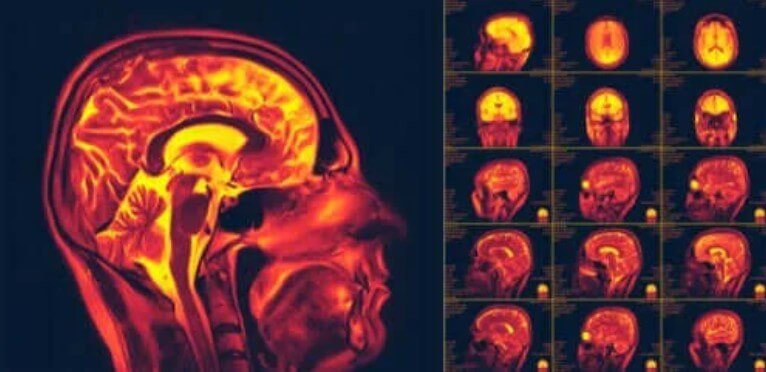

Η νευροπλαστικότητα στον εγκέφαλο, επίσης γνωστή ως εγκεφαλική πλαστικότητα, είναι μια από τις πιο σημαντικές πρόσφατες ανακαλύψεις για το ανθρώπινο σώμα. Είναι η ικανότητα του εγκεφάλου να αλλάζει και να προσαρμόζεται σε νέες συμπεριφορές ή εμπειρίες.

Ωστόσο, οι επιστήμονες ανακάλυψαν ότι οι νευρώνες του εγκεφάλου μας μπορούν να αναγεννηθούν συνεχώς. Στην πραγματικότητα, το κάνουν όχι μόνο ανατομικά, αλλά μπορούν επίσης να σχηματίσουν νέες συνδέσεις. Αυτή η ιδέα είναι κοινώς γνωστή ως «νευροπλαστικότητα». Αν και φαίνεται απλό, είναι αυτό που επιτρέπει στον εγκέφαλο να ανακάμψει από συγκεκριμένους τραυματισμούς ή διαταραχές.

Η νευροπλαστικότητα είναι η ικανότητα των νευρώνων να αναγεννιούνται. Το κάνουν τόσο ανατομικά όσο και λειτουργικά. Στην πραγματικότητα, είναι μια διαδικασία που περιλαμβάνει πολλές βιοχημικές και μεταβολικές αντιδράσεις. Επίσης, σημαίνει ότι έχει μεγάλες δυνατότητες προσαρμογής.

Η νευροπλαστικότητα αναφέρεται στον τρόπο με τον οποίο το νευρικό μας σύστημα πρέπει να σχηματίσει νέες συνδέσεις. Επιπλέον, το κάνει αυτό ως απάντηση σε νέα ερεθίσματα, πληροφορίες ή ακόμη και για να θεραπεύσει ζημιά σε παλιές συνδέσεις.

Οι επιστήμονες άρχισαν να παρατηρούν αυτό το ζήτημα τη δεκαετία του 1960. Έδωσαν προσοχή σε αρκετές περιπτώσεις ενηλίκων που είχαν υποστεί εγκεφαλικά επεισόδια. Στην πραγματικότητα, παρατήρησαν ότι, κάποια στιγμή μετά τον τραυματισμό, πολλοί φάνηκαν να αναρρώνουν. Στη συνέχεια, άρχισαν να εκτελούν διαφορετικές δοκιμές απεικόνισης και διέγερσης για να δείξουν ότι υπάρχει νευροπλαστικότητα. Οι επιστήμονες ερευνούν ακόμη όλες τις πτυχές αυτού του φαινομένου.